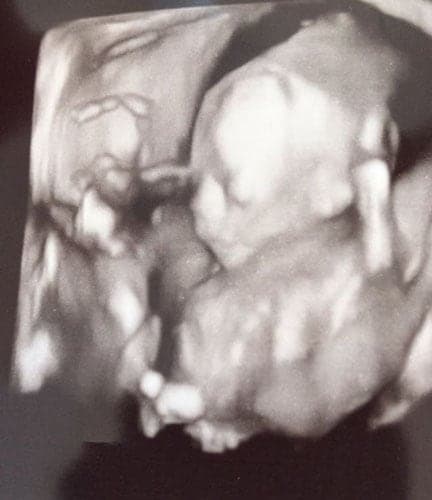

Im dritten Trimester der Schwangerschaft ist das Baby so groß, dass es nicht mehr komplett auf ein Ultraschallbild passt. Nun kann man wunderbare 3D-Ultraschalle des Gesichts machen. In diesem Semester nehmen die Babys nochmal rasant zu und wer Glück hat, kann auf seinem Ultraschall schon erste Gesichtszüge erkennen.

Was genau man auf einem Ultraschallbild erkennen kann, hängt nicht nur von der Größe des Babys ab, sondern auch davon wie gut das Ultraschall-Gerät ist, mit dem die Aufnahme gemacht wurde. Auch auf den Ultraschallbildern hier kannst du sehen, dass die Qualität stark schwankt. In der Regel kann man gut den Kopf und RUmpf des Babys erkennen und auch die Gliedmaßen erkennt man selbst als Laie gut.

Wer sich jedoch erhofft Gesichtszüge zu erkennen, der wird oft enttäuscht. Zwar kann man beim 3D-Ultraschall schon eine Menge sehen, aber das umgebende Fruchtwasser sorgt in den allermeisten Fällen für starke Störungen.